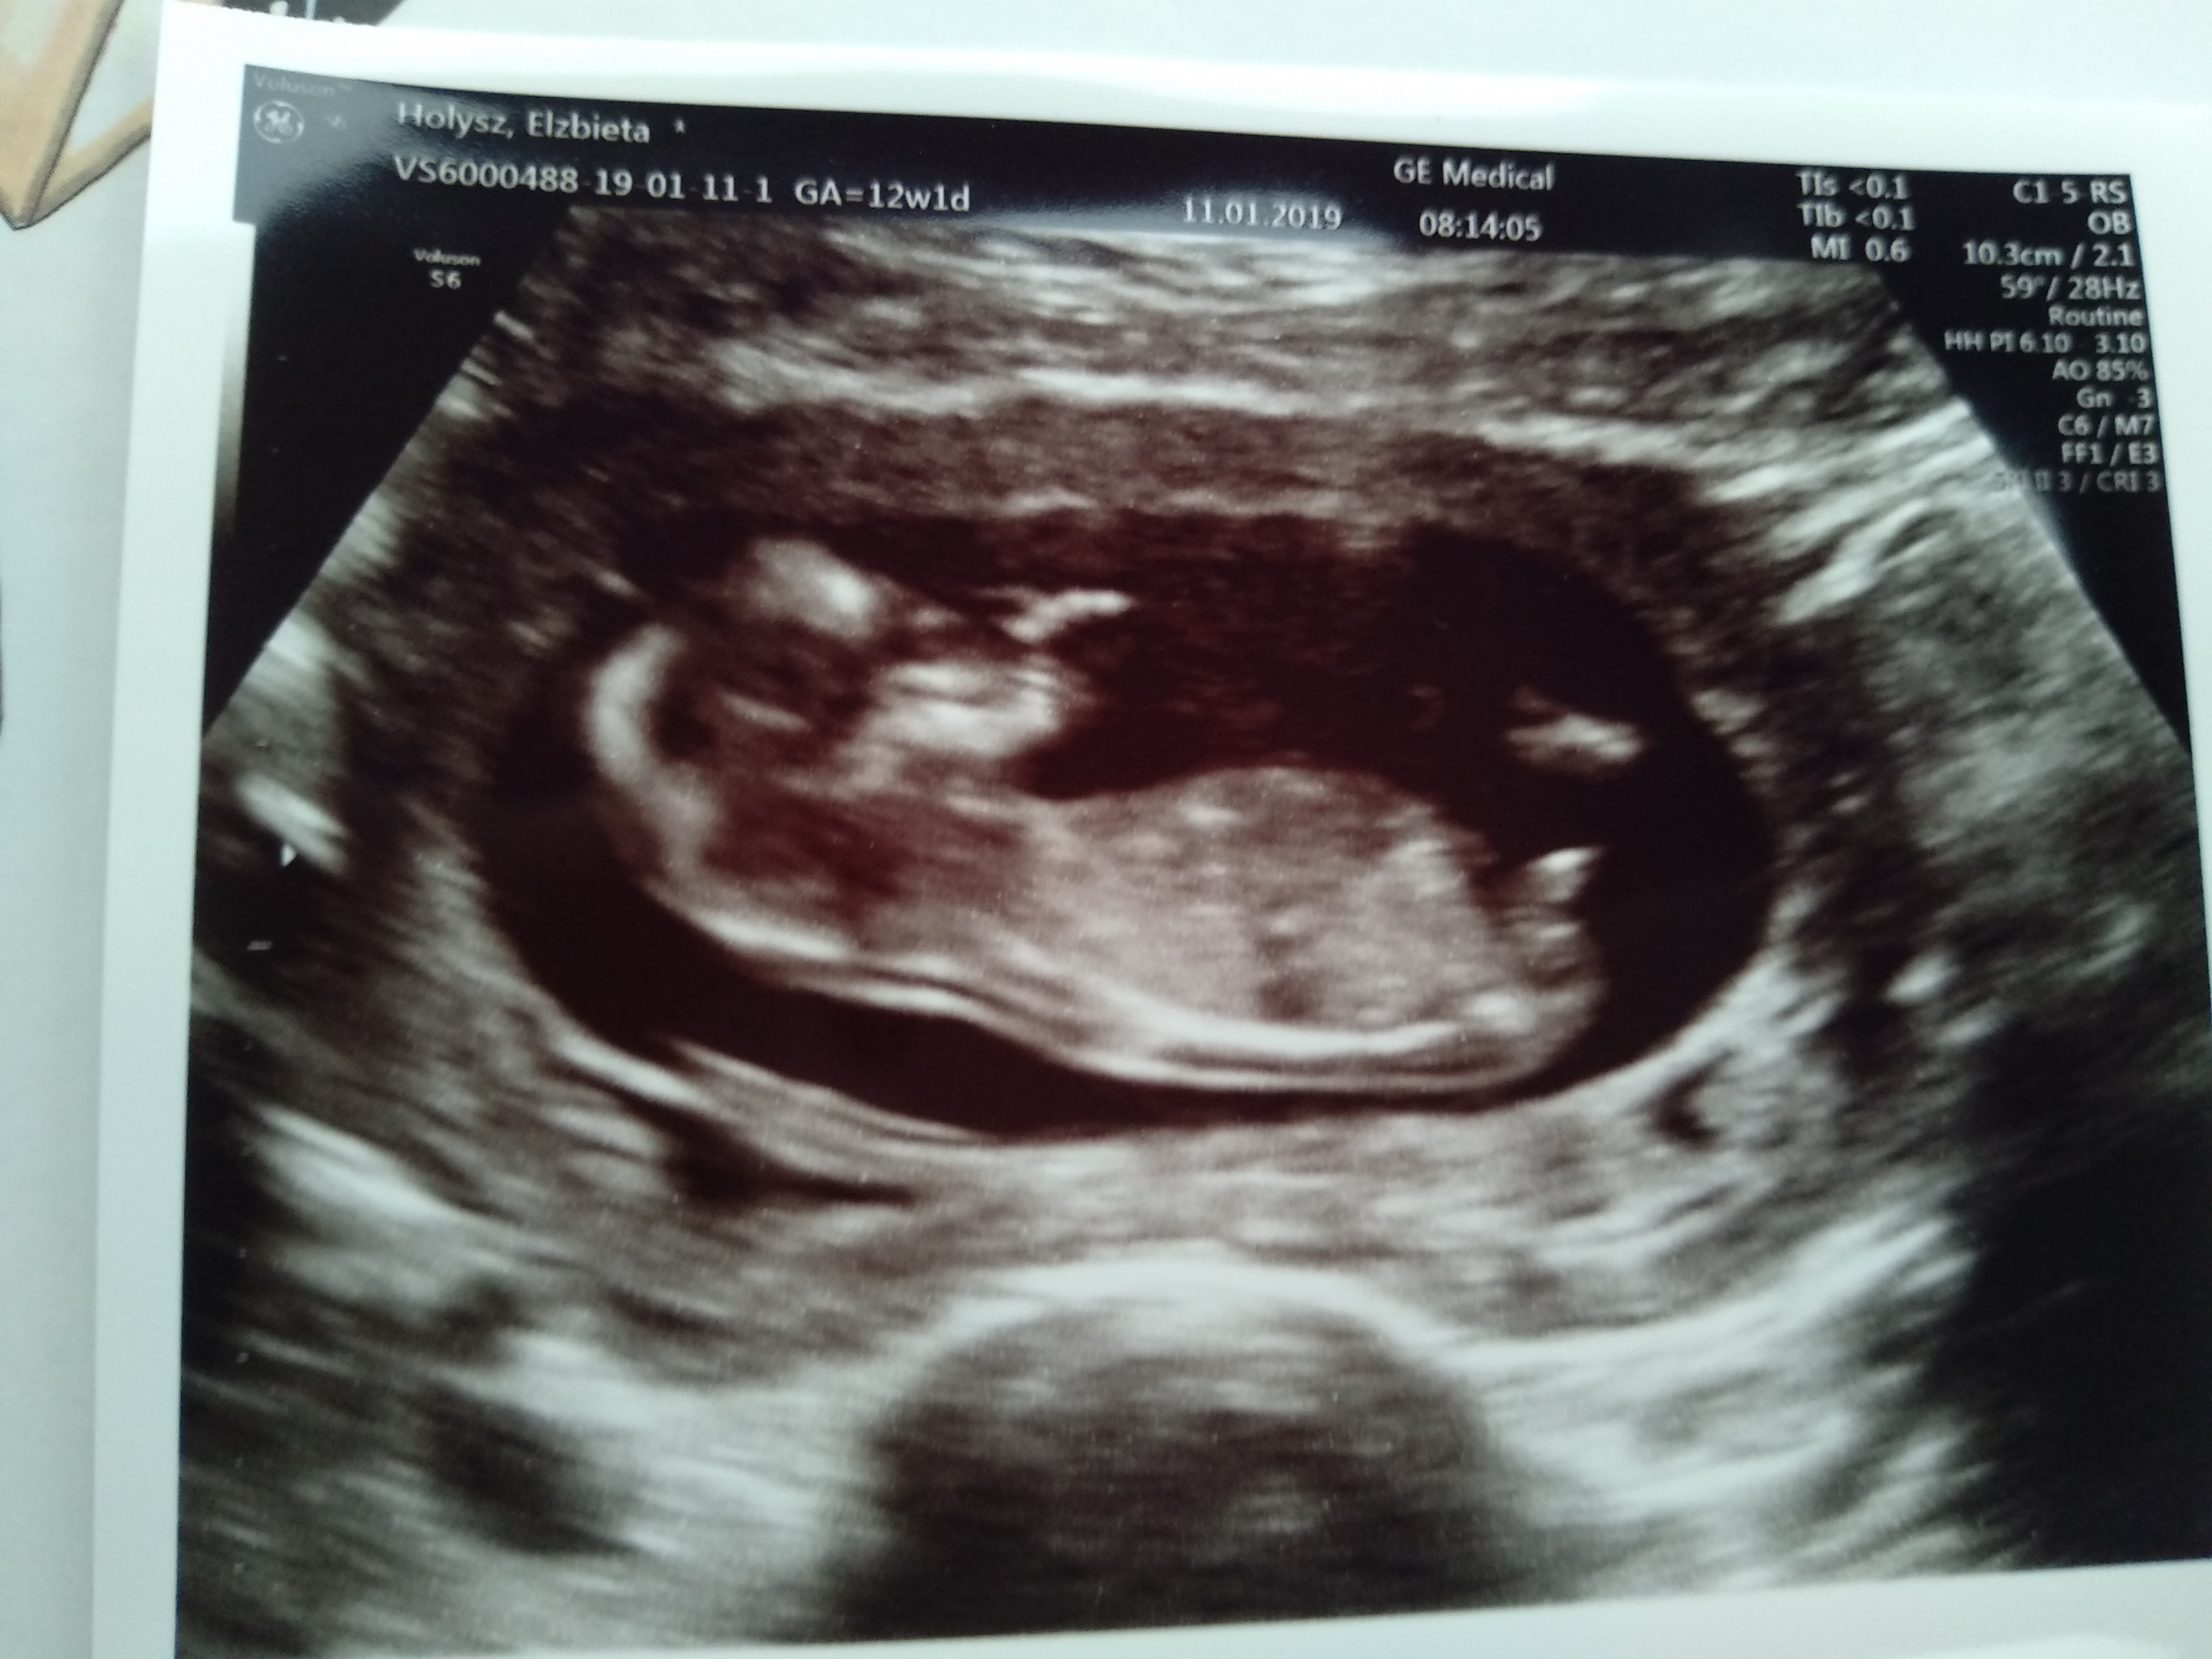

Po USG prenatalnym, które miałam na początku 13 tygodnia wyszło wszystko ok, testu pappa nie robiłam. Prawdopodobnie to będzie dziewczynka Tak bardzo się cieszę!

Mała rośnie ok. 7 cm. Piękny mały ludzik.